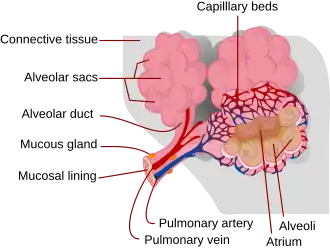

A pulmonary contusion, also known as a lung contusion, is a bruise of the lung, caused by chest trauma. As a result of damage to capillaries, blood and other fluids accumulate in the lung tissue. The excess fluid interferes with gas exchange, potentially leading to inadequate oxygen levels (hypoxia). Unlike a pulmonary laceration, another type of lung injury, a pulmonary contusion does not involve a cut or tear of the lung tissue.

Pulmonary contusion results in bleeding and fluid leakage into lung tissue, which can become stiffened and lose its normal elasticity.[37] The water content of the lung increases over the first 72 hours after injury, potentially leading to frank pulmonary edema in more serious cases.[23] As a result of these and other pathological processes, pulmonary contusion progresses over time and can cause hypoxia (insufficient oxygen).

Bleeding and edema

In contusions, torn capillaries leak fluid into the tissues around them.[38] The membrane between alveoli and capillaries is torn; damage to this capillary–alveolar membrane and small blood vessels causes blood and fluids to leak into the alveoli and the interstitial space (the space surrounding cells) of the lung.[14] With more severe trauma, there is a greater amount of edema, bleeding, and tearing of the alveoli.[20] Pulmonary contusion is characterized by microhemorrhages (tiny bleeds) that occur when the alveoli are traumatically separated from airway structures and blood vessels.[28] Blood initially collects in the interstitial space, and then edema occurs by an hour or two after injury.[34] An area of bleeding in the contused lung is commonly surrounded by an area of edema.[28] In normal gas exchange, carbon dioxide diffuses across the endothelium of the capillaries, the interstitial space, and across the alveolar epithelium; oxygen diffuses in the other direction. Fluid accumulation interferes with gas exchange,[39] and can cause the alveoli to fill with proteins and collapse due to edema and bleeding.[28] The larger the area of the injury, the more severe respiratory compromise will be.[20]

Consolidation and collapse

Pulmonary contusion can cause parts of the lung to consolidate, alveoli to collapse, and atelectasis (partial or total lung collapse) to occur.[40] Consolidation occurs when the parts of the lung that are normally filled with air fill with material from the pathological condition, such as blood.[41] Over a period of hours after the injury, the alveoli in the injured area thicken and may become consolidated.[28] A decrease in the amount of surfactant produced also contributes to the collapse and consolidation of alveoli;[19] inactivation of surfactant increases their surface tension.[35] Reduced production of surfactant can also occur in surrounding tissue that was not originally injured.[30]

Inflammation of the lungs, which can result when components of blood enter the tissue due to contusion, can also cause parts of the lung to collapse. Macrophages, neutrophils, and other inflammatory cells and blood components can enter the lung tissue and release factors that lead to inflammation, increasing the likelihood of respiratory failure.[42] In response to inflammation, excess mucus is produced, potentially plugging parts of the lung and leading to their collapse.[28] Even when only one side of the chest is injured, inflammation may also affect the other lung.[42] Uninjured lung tissue may develop edema, thickening of the septa of the alveoli, and other changes.[43] If this inflammation is severe enough, it can lead to dysfunction of the lungs like that seen in acute respiratory distress syndrome.[44]

Ventilation/perfusion mismatch

Normally, the ratio of ventilation to perfusion is about one-to-one; the volume of air entering the alveoli (ventilation) is about equal to that of blood in the capillaries around them (perfusion).[45] This ratio is reduced in pulmonary contusion; fluid-filled alveoli cannot fill with air, oxygen does not fully saturate the hemoglobin, and the blood leaves the lung without being fully oxygenated.[46] Insufficient inflation of the lungs, which can result from inadequate mechanical ventilation or an associated injury such as flail chest, can also contribute to the ventilation/perfusion mismatch.[35] As the mismatch between ventilation and perfusion grows, blood oxygen saturation is reduced.[46] Pulmonary hypoxic vasoconstriction, in which blood vessels near the hypoxic alveoli constrict (narrow their diameter) in response to the lowered oxygen levels, can occur in pulmonary contusion.[31] The vascular resistance increases in the contused part of the lung, leading to a decrease in the amount of blood that flows into it,[43] directing blood to better-ventilated areas.[31] Although reducing blood flow to the unventilated alveoli is a way to compensate for the fact that blood passing unventilated alveoli is not oxygenated,[31] the oxygenation of the blood remains lower than normal.[45] If it is severe enough, the hypoxemia resulting from fluid in the alveoli cannot be corrected just by giving supplemental oxygen; this problem is the cause of a large portion of the fatalities that result from trauma.[46]